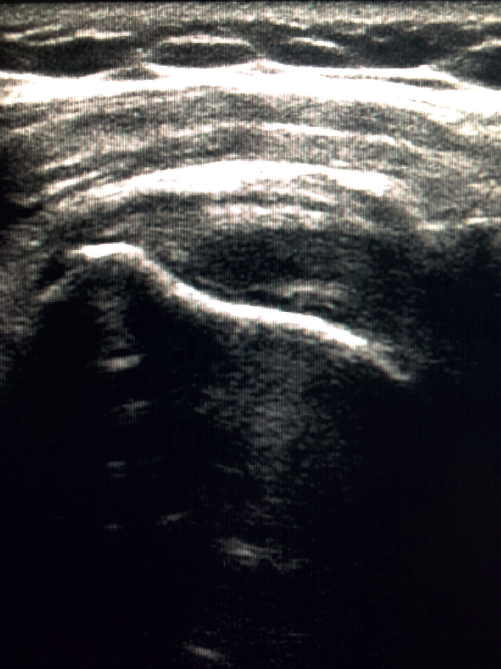

Figure 3. Ultrasound view of severe supraspinatus tendinopathy, with associated bursitis.

The characteristic ultrasound image of tendinosis consists of local or diffuse thickening accompanied by a hypoechogenic and heterogeneous appearance of the tendon (Figure 3). A fine hypoechoic line over 2 mm in thickness between the tendon of the supraspinatus and the subdeltoid adipose tissue corresponds to subacromial-subdeltoid bursitis, and the presence of fluid in the bursa is related to a high probability of partial or complete injury of the tendon of the supraspinatus muscle(26). In order to achieve greater diagnostic accuracy and distinguish between an inflammatory process and a normal small amount of fluid in the bursa, we should take into account that bursitis, tenosynovitis and tendinitis are characterized by the presence of hyperechoic zones with areas of enhanced flow in the Doppler ultrasound study. Both bursal and articular partial ruptures appear as a hypoechoic discontinuity in the tendon that does not vary on modifying the inclination of the ultrasound probe in either the long axis of the tendon nor its short axis(19). This latter aspect is important in order not to confuse partial lesions with anisotropic phenomena, which are a change in tissue behaviour according to the ultrasound angle of incidence(27)(Figure 4).